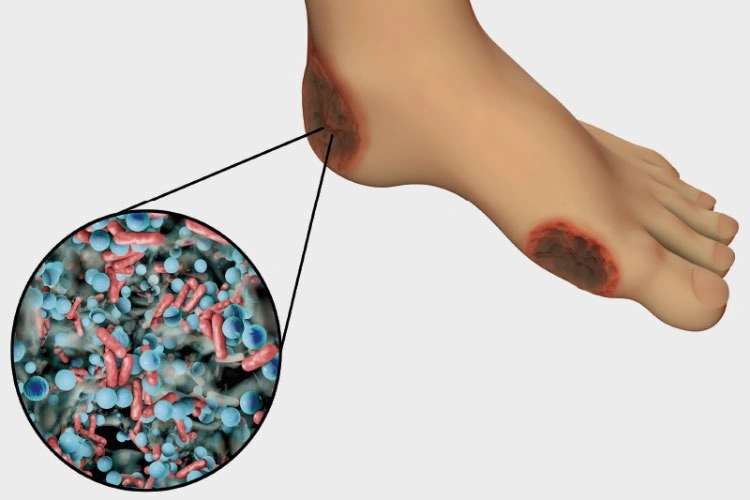

وهو ما يطلق عليها (Dry gangrene) وهو أكثر الأنواع شيوعًا، بالأخص بين مرضى السكر والأوعية الدموية وأمراض المناعة الذاتية، ينتشر هذا النوع في اليدين والقدمين ويكون سببه الرئيسي عدم وصول الدم لهذه الأجزاء أو ضعفه فيها؛ مما يُميت الأنسجة ويغير لونها، وجدير بالذكر أنه يمكن تطور هذا النوع إلى الغرغرينا الرطبة بأنوعها المختلفة.

تعرف باسم (Wet gangrene) وهي تنشأ عن عدوى بكتيرية في الغالب أو التعرض لإصابة ما، مثل الحروق التي تقلل من تدفق الدم للأنسجة المصابة، وقد سُمي هذا النوع بالرطب بسبب الصديد والإفرازات الناتجة عنه، وهو سهل الانتشار لجميع أجزاء الجسم، أما عن أنواعه فهي كالآتي:

- البحث بشكل يومي عن آثار جروح، أو تقرحات جلدية ظاهرة، أو احمرار، أو تورم، أو أية تشققات في الجلد، أو إفرازات من القدمين، حيث يعتبر كل ما سبق هو إشارات على وجود الإصابة التي تستوجب مراجعة الطبيب بشكل فوري.

- الكشف عن وجود إصابات تلف عصبي لمرضى السكر خاصة في القدمين إذ قد ينشأ عنها غرغرينا.